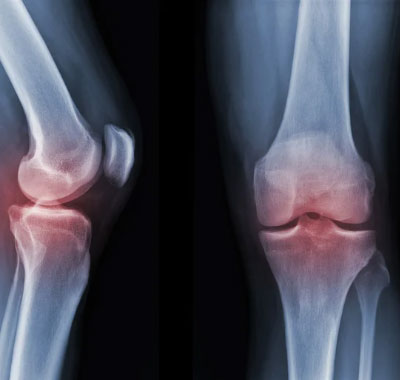

- خشونة المفاصل وتآكل الغضاريف

- جراحات استبدال المفاصل (الركبة – الفخذ)